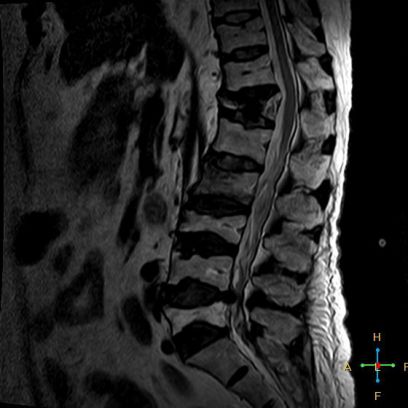

3 恶性压缩性骨折 椎体上下径变窄而前后径增大,椎体后部皮质后突,后角一般表现圆钝,无上翘,常呈球形突出,致椎管狭窄,即膨胀性盘状破坏,硬膜囊和脊髓受压。

——恶性压缩性骨折MR信号特点—— 由于肿瘤组织的侵犯,T1WI上椎体呈弥漫性低信号,T2WI呈高信号,增强扫描呈明显不均匀强化。

转移瘤 椎弓根改变:椎弓根膨大仅见于恶性压缩性骨折,故为其特异性,可作为鉴别诊断的依据。

椎旁软组织肿块:在转移瘤中,受累椎体周围多出现分叶状或肿瘤样软组织肿块,此征象仅见于恶性压缩性骨折。故,椎旁薄环状软组织与瘤样软组织肿块是鉴别骨折性质较有特征性的征象。

4 总结:鉴别诊断 ——良性压缩性骨折—— 楔形或凹陷形 连续性分布 椎间盘增厚双凸状,许莫氏结节 急性期T1WI不均匀低信号 椎体后角翘起突入椎管内 椎体后角回避现象 可伴椎弓根水肿、无膨大 椎旁薄环形软组织影

——恶性压缩性骨折—— 扁平形或倒楔形 跳跃性分布(转移瘤) 椎间盘不受累 T1WI均匀低信号 后角圆钝,膨胀性盘状破坏 椎弓根受累、膨大 椎旁分叶状及肿瘤样软组织肿块